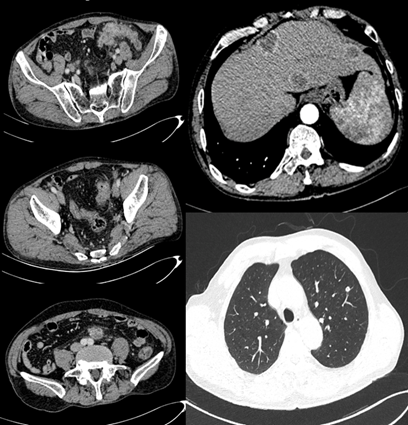

2017-09-13 下腹部CT增强:降结肠及乙状结肠交界处肠壁增厚,邻近系膜增厚及淋巴结显示。近段小肠系膜上肿块影,约21*44mm,增强扫描轻度强化。少量腹水。

2017-09-13 上腹部CT增强:肝脏多发稍低密度影,大者直径约32mm,CT值约30HU,增强扫描边缘明显强化。肝脏多发占位,转移瘤可能。

2017-9-13 胸部CT增强:左肺上叶可疑孤立结节影,约8mm,轻度强化。